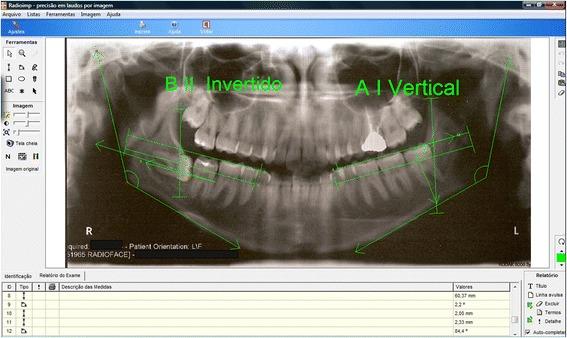

A retrospective cohort study was performed. The sample was collected from a database of patients covered by Medical Fund of Brazilian Army. Radiographs were obtained a minimum of 5 years prior to the presurgical visit and after their clinical exam. The primary outcome variables were the teeth positions using Pell and Gregory/Winter classifications on panoramic X-rays. Those variables were analyzed at both the beginning (T0) and end of the study (T1). Clinical assessments and histopathological study of the thirds that were extracted were performed only at T1. Correlation between the teeth positions were related to the clinical, histopathological, and radiographic parameters using statistical analysis tests with significance set at p < 0.05.

Twenty-six patients with 49 M3 were assessed over 10 months. Mean age was 14.92 years at T0 and 21.87 years at T1. The average time between T0 and T1 was 6.77 years. A significant relationship (p = 0.024) was found between the presences of root resorption on the second molar if M3 presented in an IB horizontal position at T1. There was also a significant correlation (p = 0.039) between dental crowding of the anterior lower teeth with IIIB position at T0 and if the patient finished orthodontic treatment without lingual retainers.

Lower M3 in position IIIB seen in a teenager and IB seen in an adult is more likely to have negative consequences and should be followed closely.